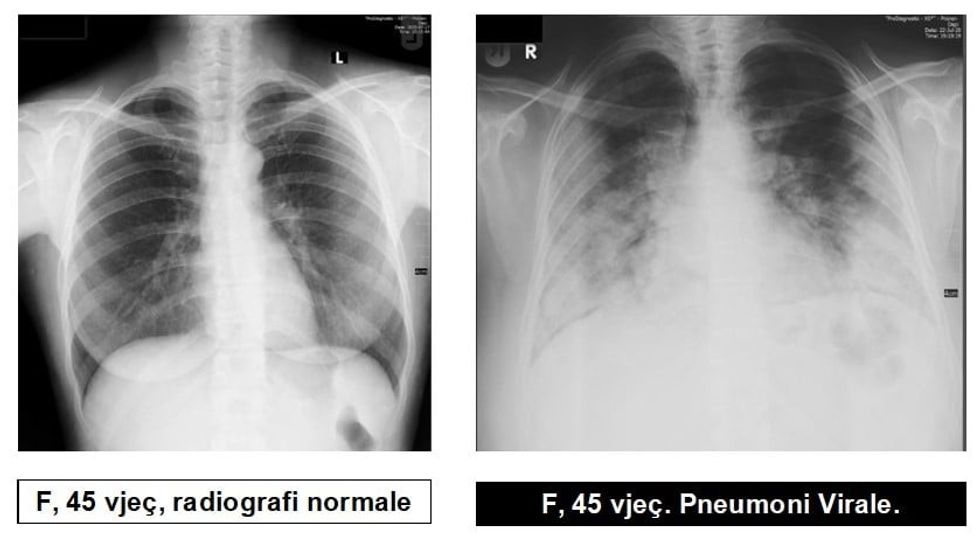

Radiologu në Spitalin Rajonal të Prizrenit, Sylejman Krasniqi tregon pamjet e mushkërive të pacientëve me pneumoni virale.

“Për te gjithë ata që maskat i kane veç si dekorim, për ata që distancën sociale e kanë diçka të huaj dhe për të gjithë ata që nuk i respektojnë këshillat e institucioneve relevante Shëndetësore, këto imazhe le të ju shërbejnë që ta kuptoni se megjithatë virus ka, pandemi ka dhe situata nuk është e mirë”, ka shkruar Krasniqi, përcjell Telegrafi.